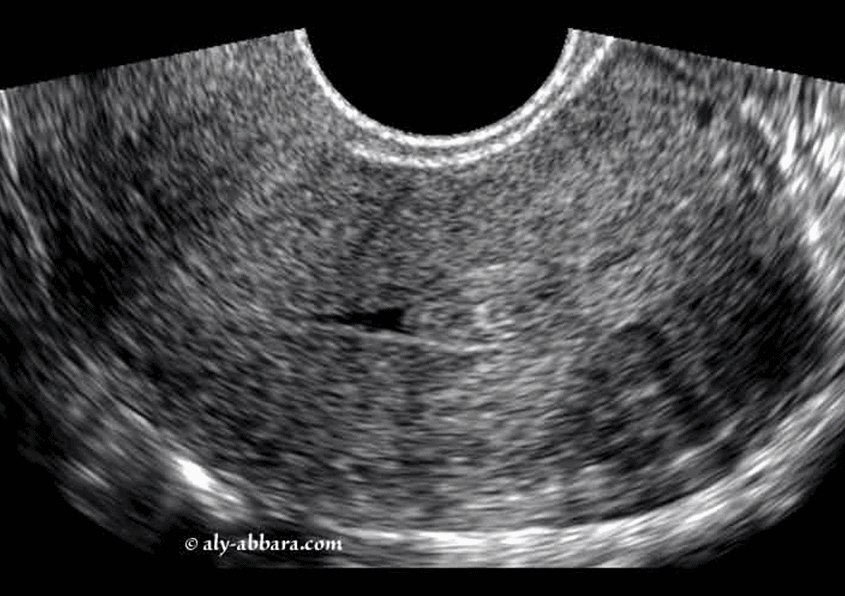

Fibrome endocavitaire, sous muqueux pédiculé (classe 0 de FIGO) du fond de l'utérus

Images montrant un fibrome utérin endocavitaire, sous muqueux pédiculé (classe 0 de FIGO) de 14 x 12,3 x 7 mm de diamètre, soit 0,63 cm3.

Il s'agit d'images permettant de comparer l'aspect échographique à l'aspect anatomique hystéroscopique avec grossissement ; puis l'image qui suit immédiatement montre l'aspect hystéroscopique du fond la cavité utérine, et en particulier, le site d'insertion du pédicule de ce fibrome déjà sectionné par myomectomie hystéroscopique à l'aide de l'anse de résection mono-polaire.